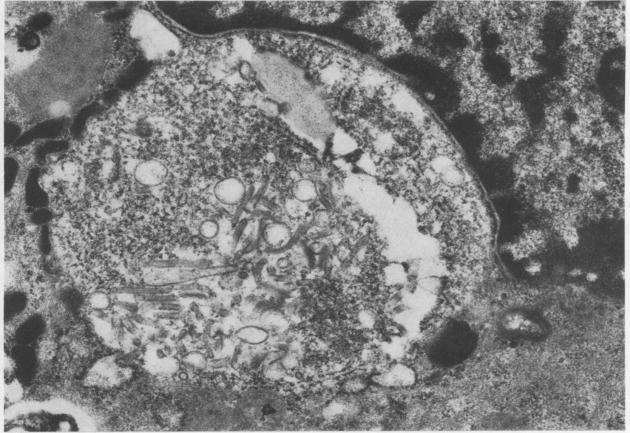

Opportunistic protozoan infections in human immunodeficiency virus disease: review highlighting diagnostic and therapeutic aspects.

摘要